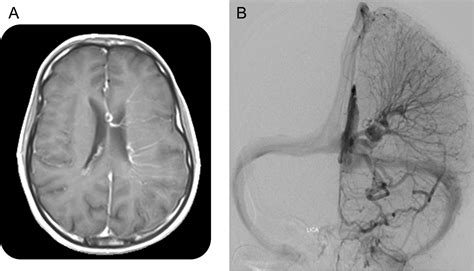

Diagnosing a DVA typically involves imaging studies, such as magnetic resonance imaging (MRI) or computed tomography (CT) scans. These imaging techniques can reveal the characteristic appearance of DVAs, which include:

In some cases, additional imaging studies, such as angiography, may be performed to better visualize the venous drainage patterns and rule out other vascular malformations.